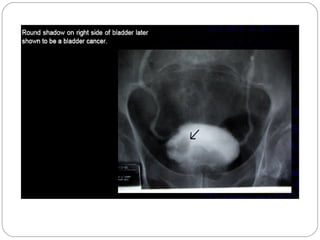

Bladder transitional cell

carcinoma.

 Bladder image shows a filling

defect with a papillary

configuration along the right

bladder wall

 Note the irregular distribution

of contrast material

 associated with the filling

defect (“stipple sign”)

Bladder transitional cell carcinoma

.